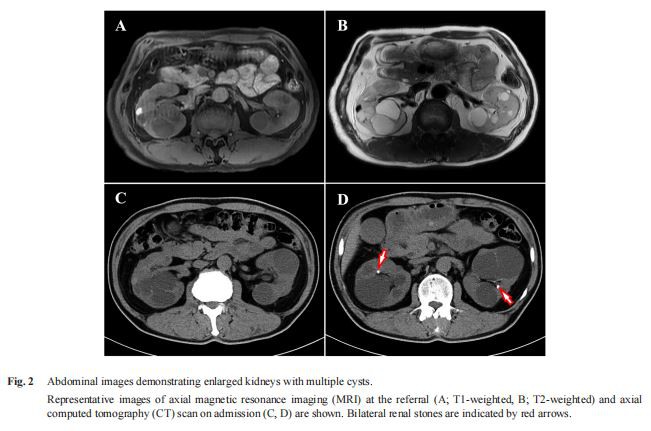

Pada lawatan pertamanya, UPCRnya dinaikkan kepada 1.20 g/GCR serentak dengan penurunan eGFR (40 mL/min/1.73 m2 ). Ultrasonografi perut dan pengimejan resonans magnetik (MRI) mendedahkan buah pinggang yang diperbesarkan dengan pelbagai sista dua hala (Rajah 2A, 2B), yang mencadangkan PKD. Anggaran jumlah isipadu buah pinggang (TKV) ialah 1,078 mL. Biopsi buah pinggang tidak dilakukan kerana banyak sista buah pinggang. Selepas peningkatan sementara kawalan glisemiknya mungkin disebabkan oleh panduan pemakanan tambahan, HbA1cnya meningkat semula, dan UPCRnya meningkat dengan cepat (Rajah 1). Semasa susulan, temu bual semula yang teliti mendedahkan bahawa pesakit telah melihat pembesaran secara beransur-ansur pada tangan dan kakinya selama beberapa tahun. Sebagai tambahan kepada diabetes bukan bergantung kepada insulin yang refraktori rawatan, ciri mukanya yang kasar dan pembesaran tangan dan kaki membawa kepada syak wasangka akromegali. Oleh itu, beliau telah dimasukkan untuk penilaian lanjut.

Data buah pinggang mendedahkan bahawa UPCR dan eGFR masing-masing adalah 4.79 g/GCR dan 43 mL/min/1.73 m2. Imbasan tomografi berkira (CT) abdomen menunjukkan pertumbuhan sista buah pinggang serta dua halabuah pinggangbatu(Gamb. 2C, 2D). Anggaran TKV ialah 1,180 mL. Angiografi resonans magnetik (MRA) otak menunjukkan pelebaran aneurisma fusiform segmen A2 proksimal arteri serebral dan basilar anterior kiri. Ekokardiografi mendedahkan hipertrofi ventrikel kiri tanpa keabnormalan injap yang jelas.